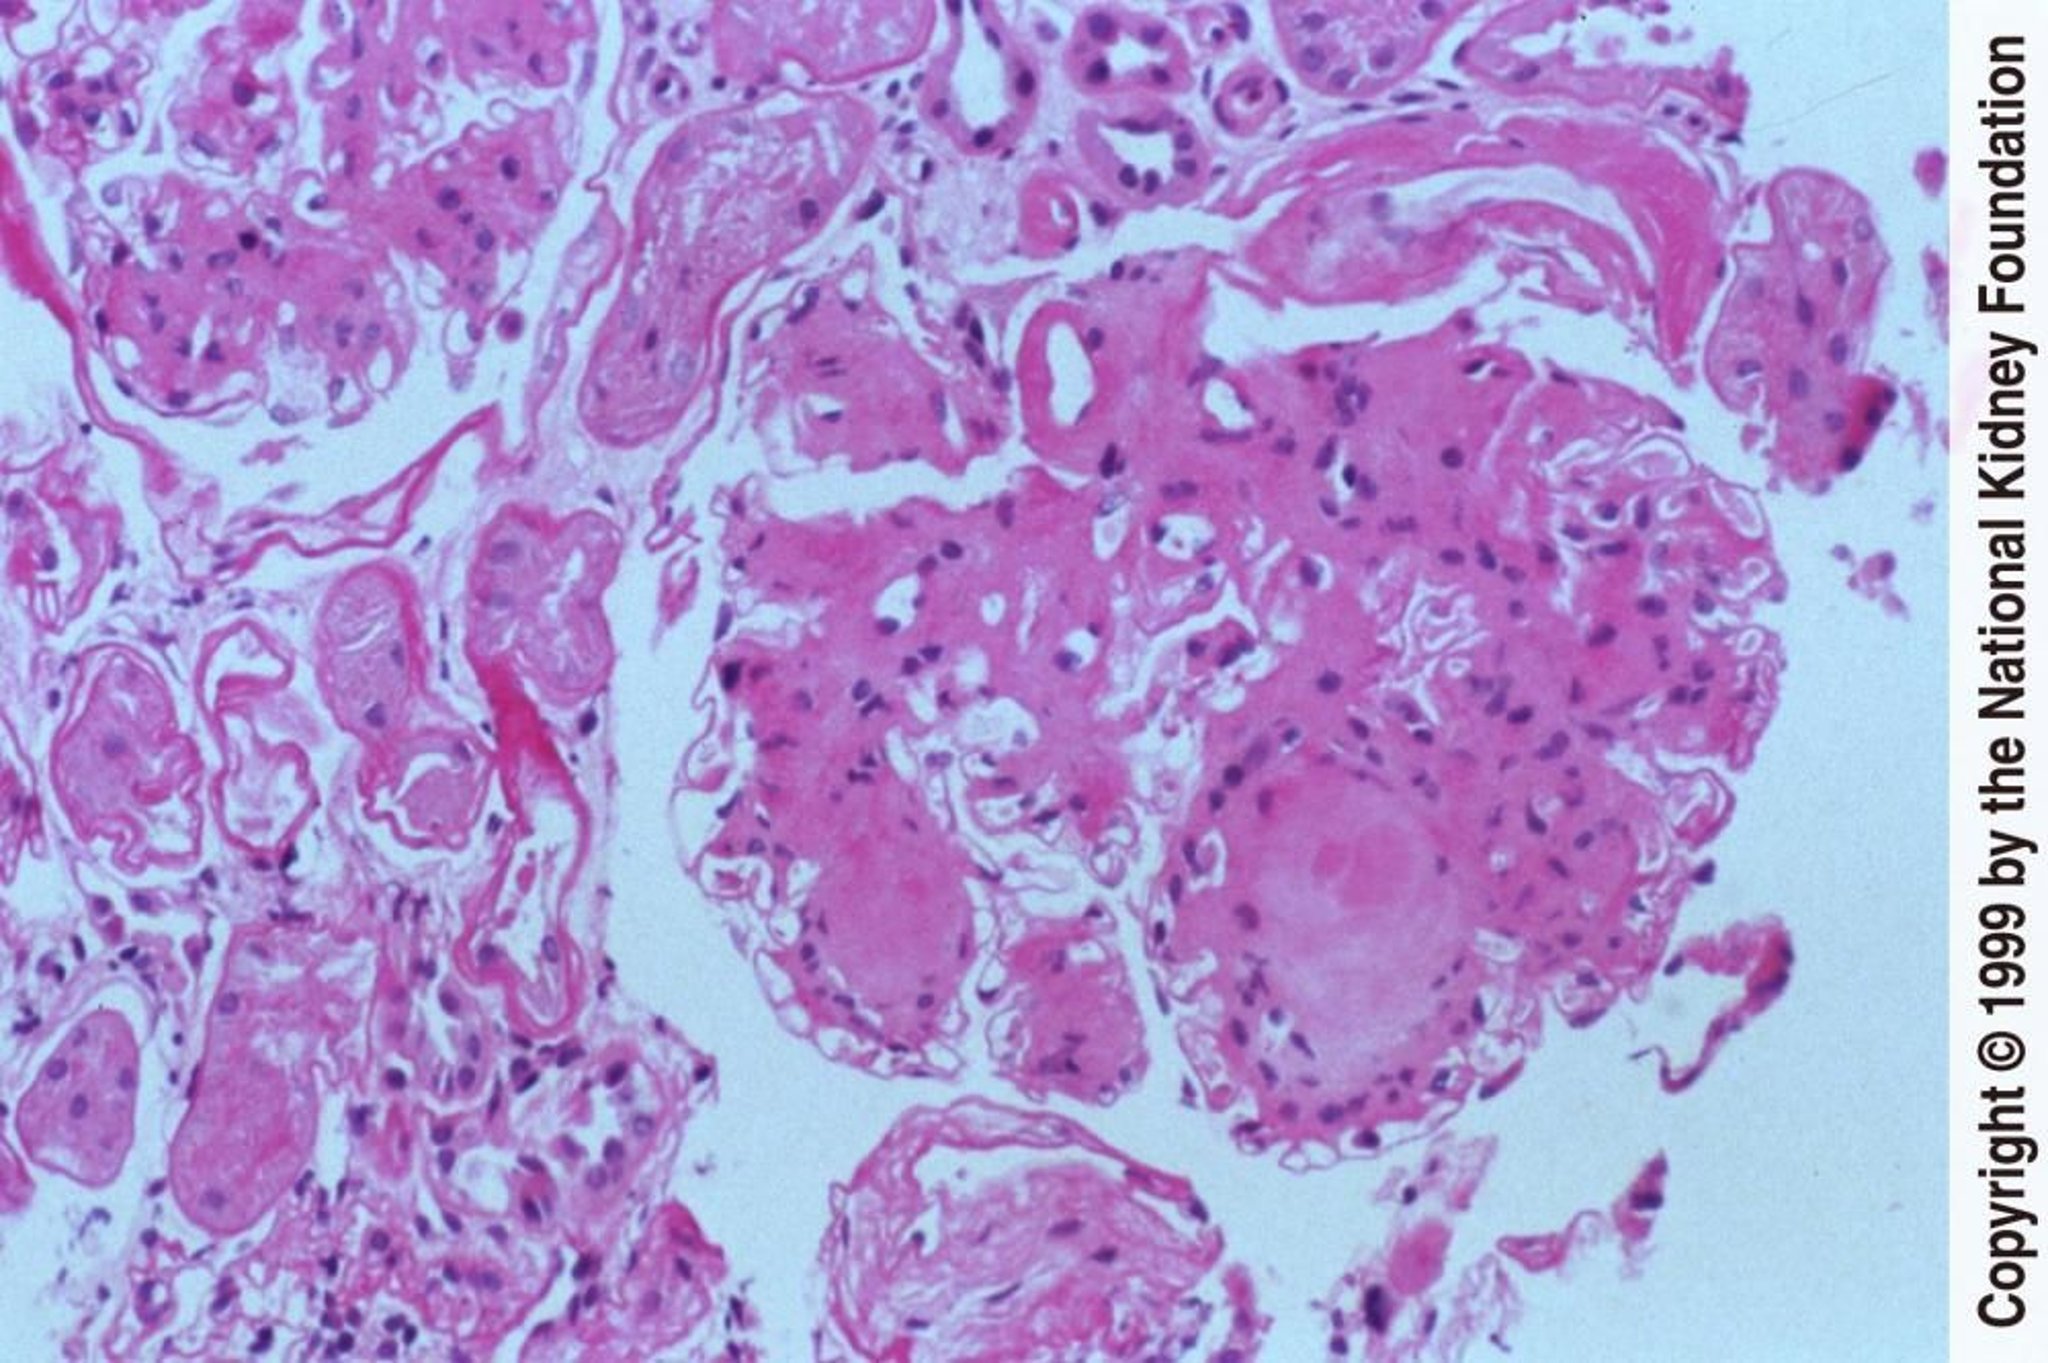

Nefropatía diabética (nódulos)

La formación de nódulos acelulares dentro de la matriz mesangial es una característica distintiva de la nefropatía diabética (tinción de ácido peryódico de Schiff, ×200).

Image provided by Agnes Fogo, MD, and the American Journal of Kidney Diseases' Atlas of Renal Pathology (véase www.ajkd.org).